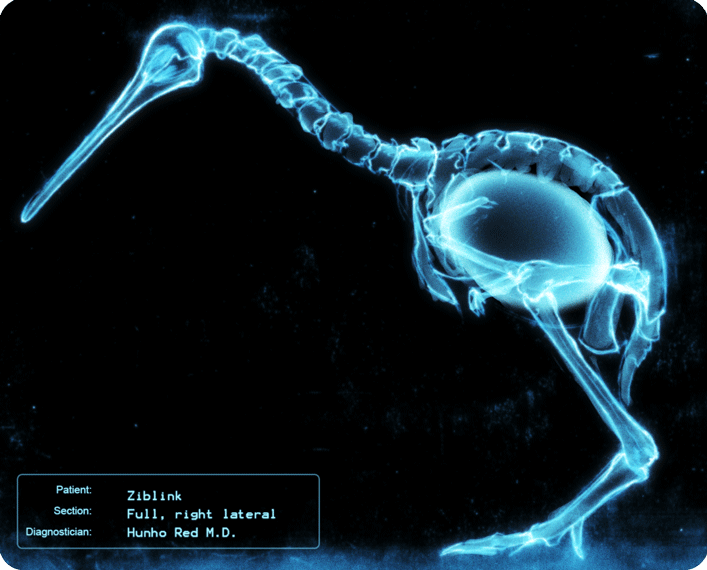

Desde su descubrimiento en 1895 por parte del profesor alemán Wilhelm Röntgen los rayos X han jugado un papel fundamental en las sociedades humanas. Son usados en campos tan distintos como el sanitario, la seguridad en el transporte e incluso la identificación de obras de arte. Su utilización está tan extendida que a veces deja imágenes tan curiosas como las recogidas en esta galería.